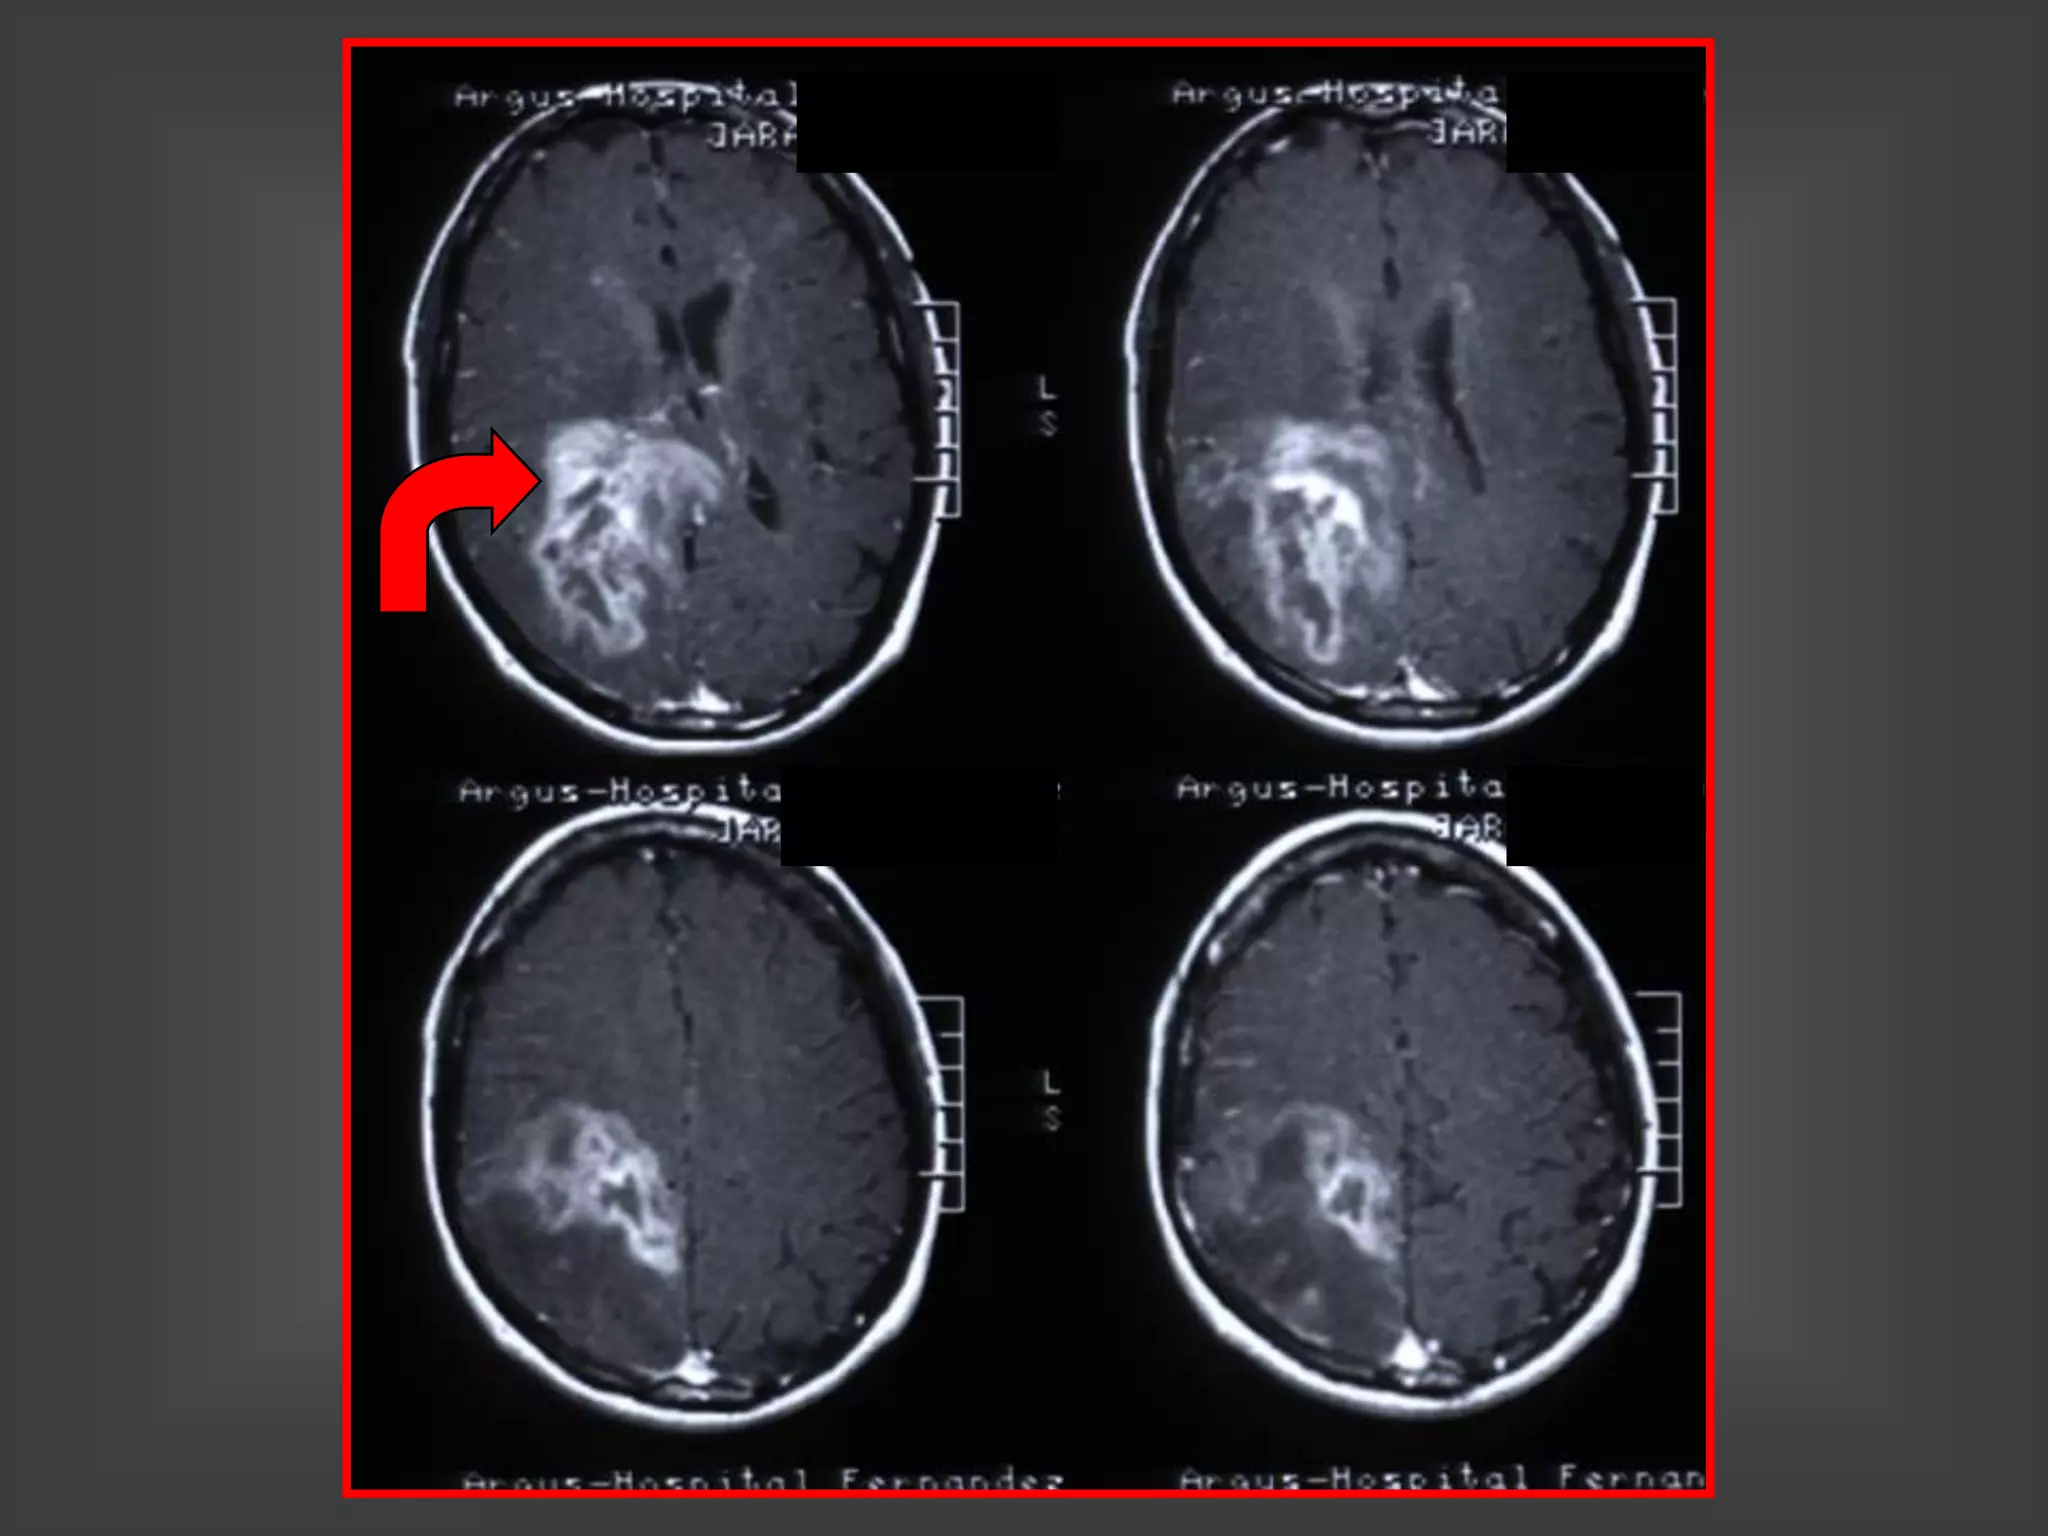

CHAGOMA - ESPECTROSCOPIA

CHAGOMA CEREBRAL

ESPECTROSCOPIA

CHAGOMA DE CUERPO CALLOSO

CHAGOMAS CEREBRALES

ENFERMEDAD DE CHAGAS

y SIDA

ABSCESOS CEREBRALES FOCALES

MENINGOENCEFALITIS DIFUSA

AMASTIGOTES EN BIOPSIA

CEREBRAL

TRIPOMASTIGOTES EN LCR